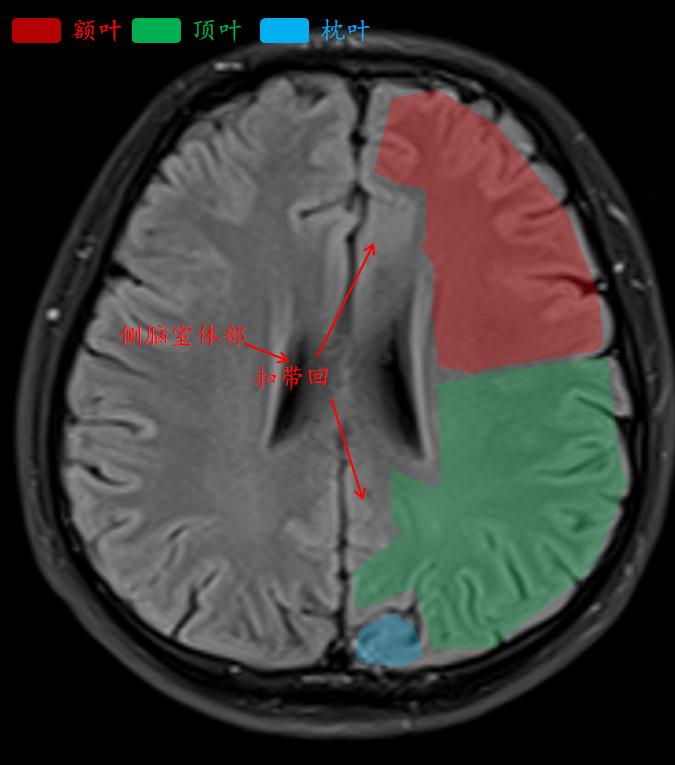

中央沟是额叶和顶叶的分界线。

顶枕沟把顶叶和枕叶分开。